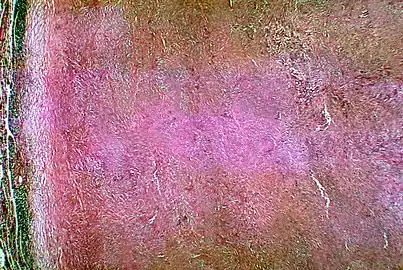

![]() | |

| A skin lesion due to Coccidioides infection | |